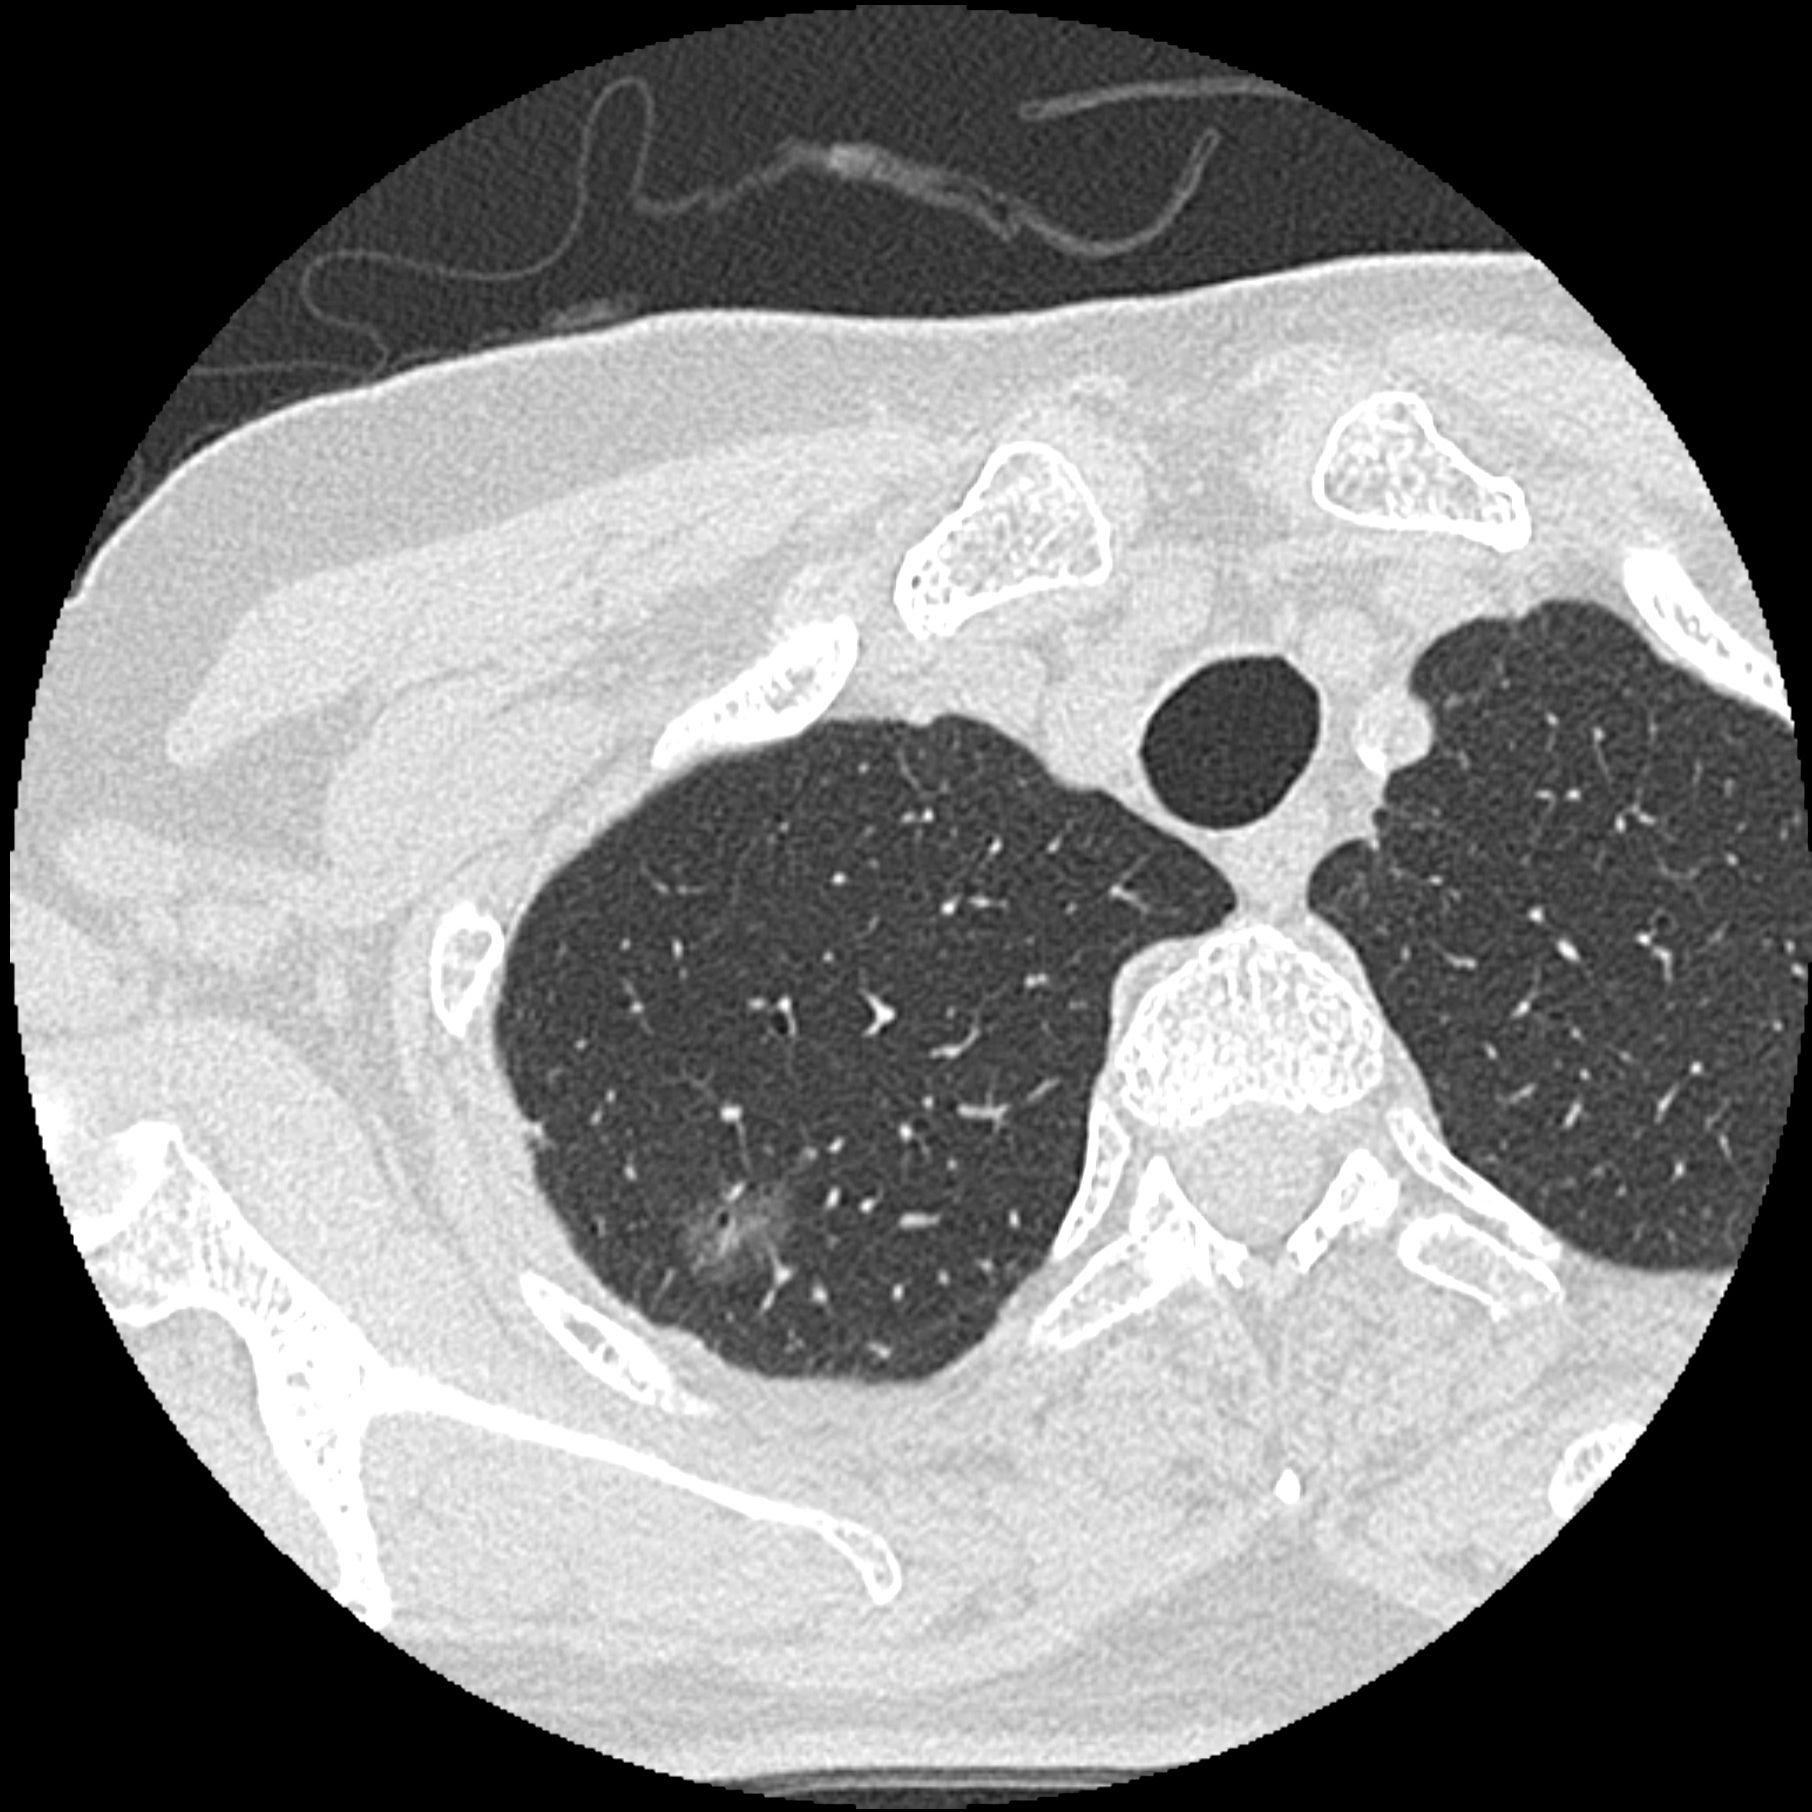

PCCTの肺がん疑い症例

a 胸部CT画像5mm厚